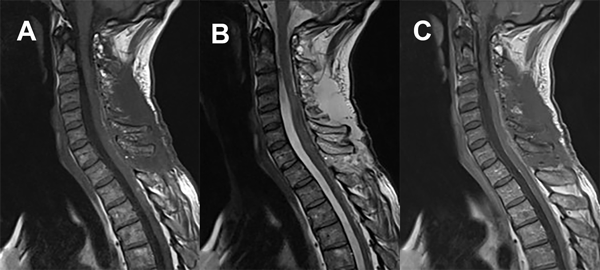

En el estudio de RM de encéfalo con contraste se describe atrofia del parénquima cerebral de forma generalizada asociado a hidrocefalia ex vacuo, sin otra aclaración a destacar. A nivel de la RM cervical con contraste se observa lesión ocupante de espacio intradural intramedular con extensión desde C3 a C7 de 12.2 mm x 9.7 mm x 20.7 mm, con efecto de masa sobre el tejido medular espinal en dichos niveles, comportándose como hiperintensa tanto en T1 como en T2, con captación tras la inyección del medio de contraste, sin evidencia de edema perilesional (Figura 1).

Figura 1. RM de columna cervical. A) Secuencia T1. Corte sagital. B) Secuencia T2. Corte sagital. C) Secuencia T2. Corte axial. D) Secuencia T1 con contraste. Corte sagital.